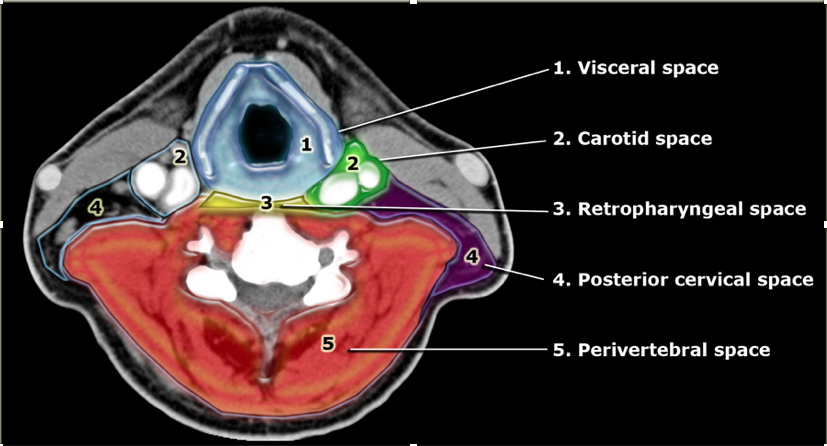

What are the contents of the carotid sheath?